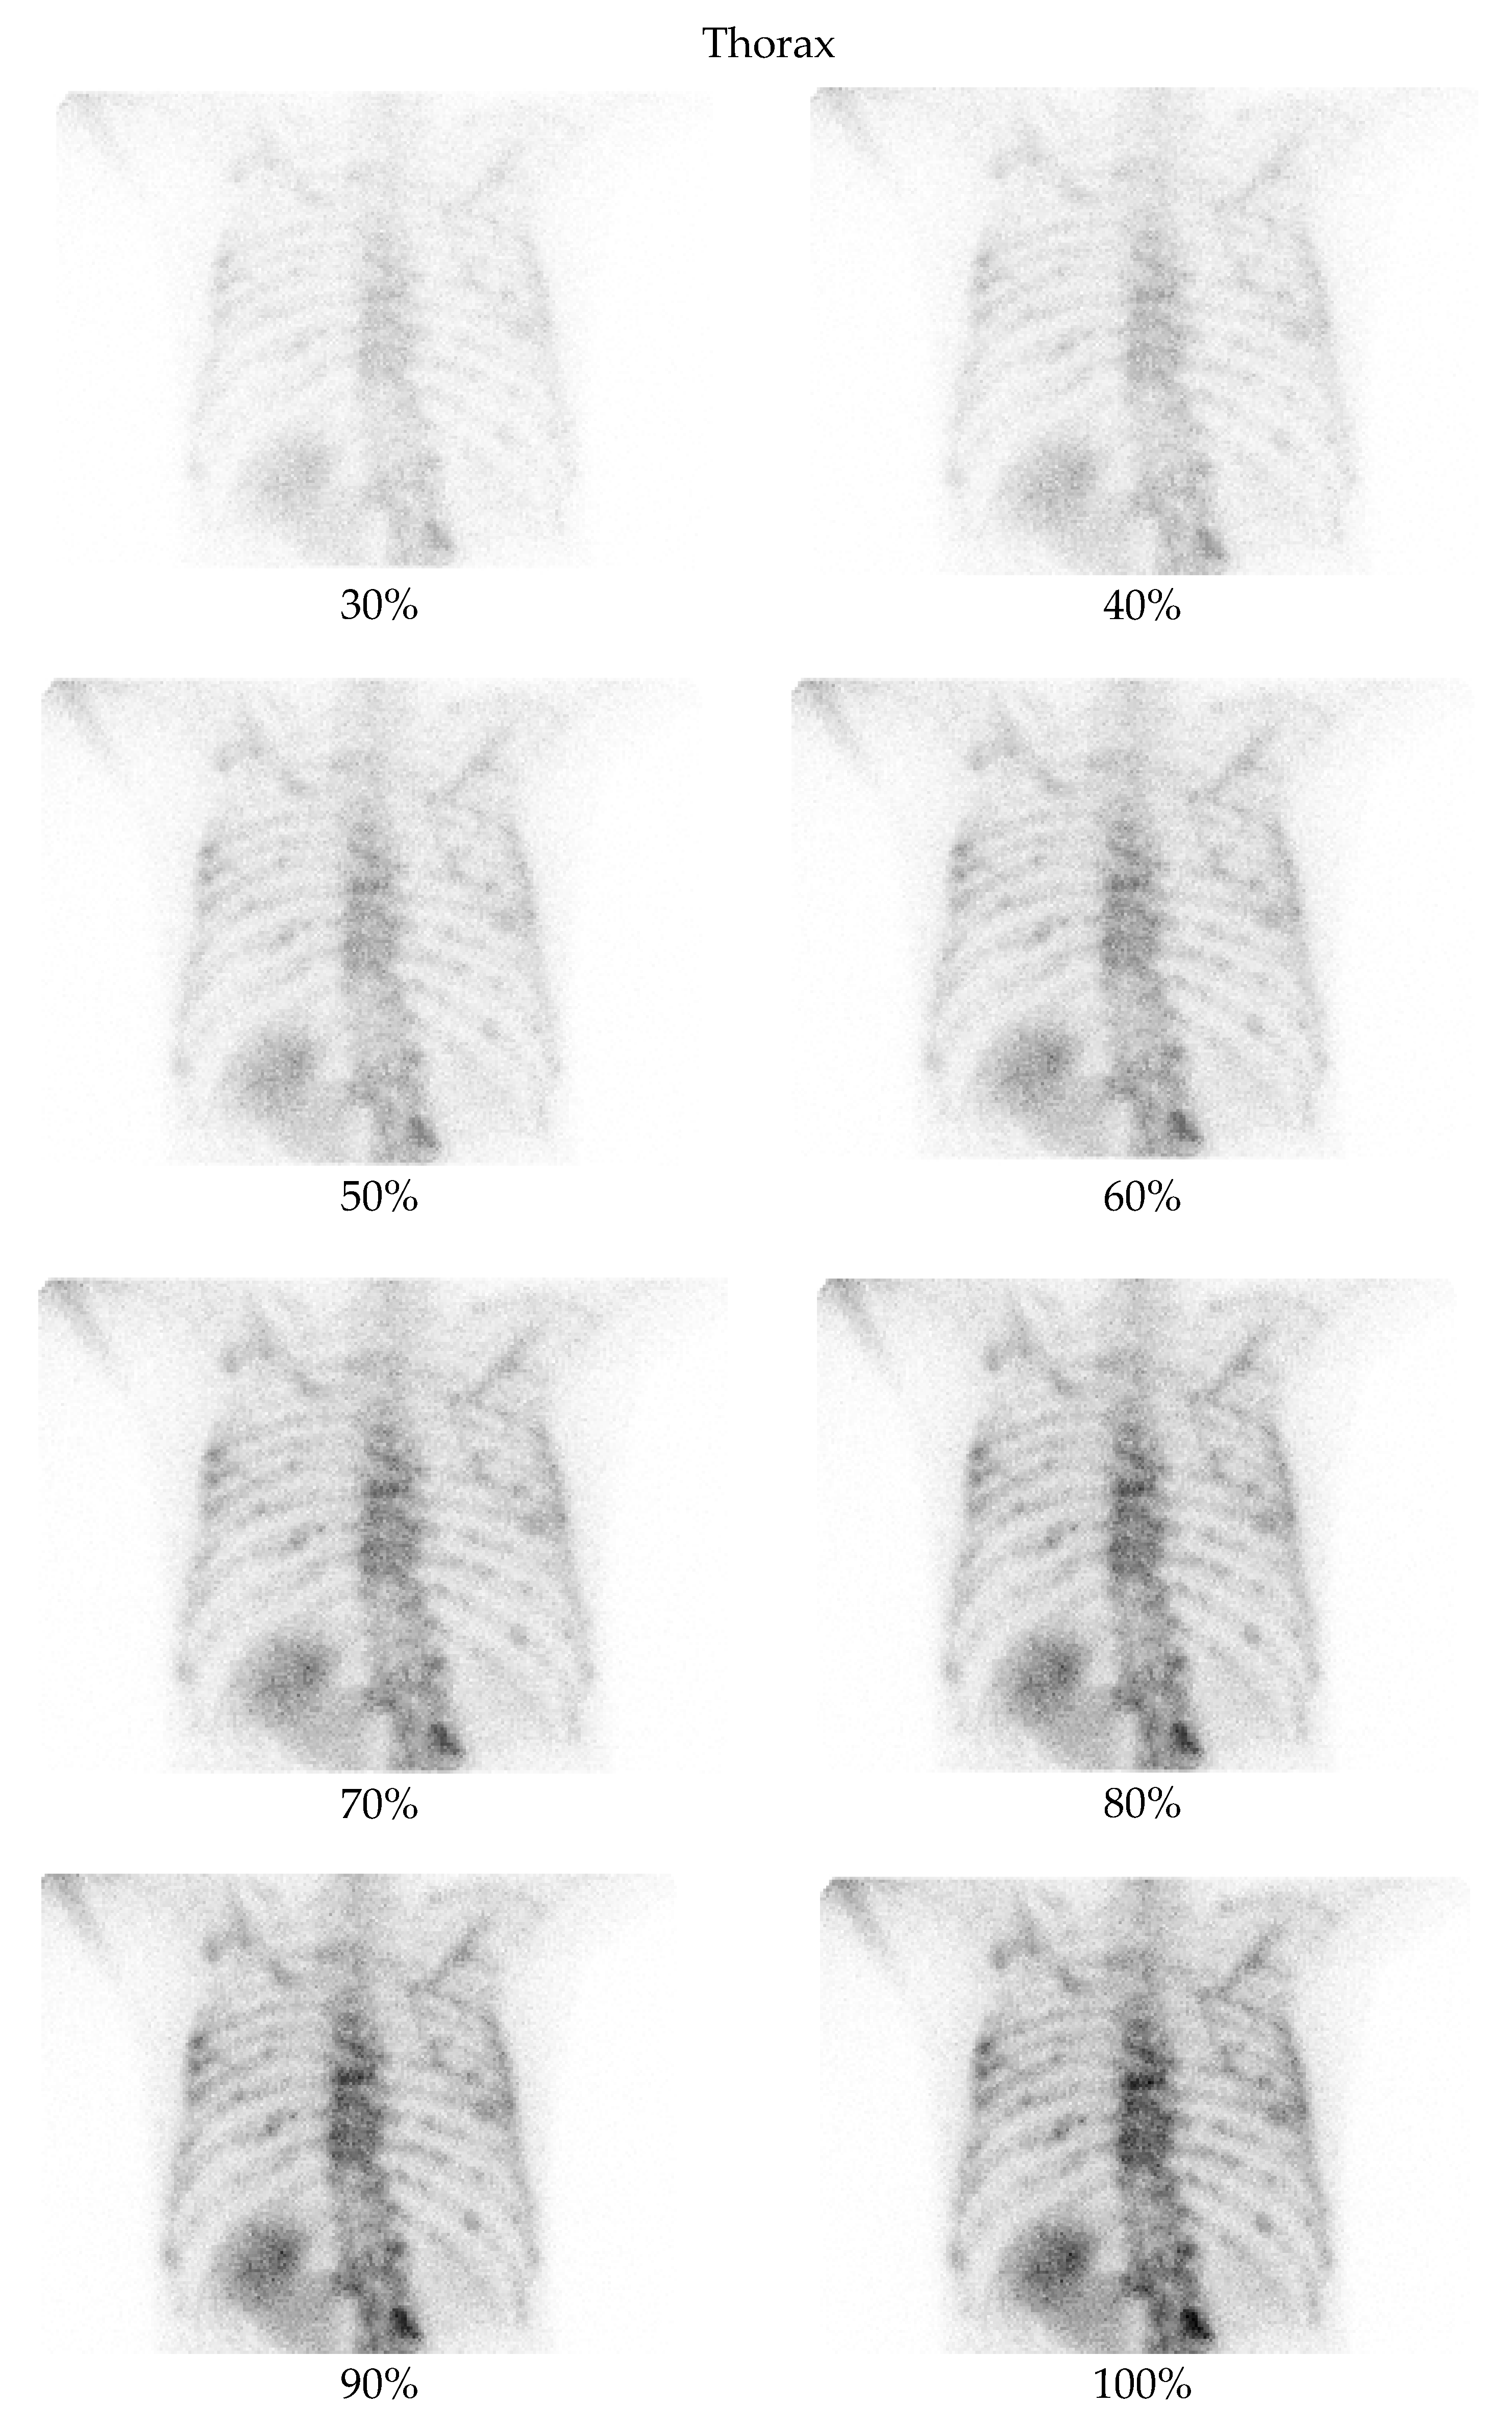

3.2. Qualitative Evaluation

- Thorax at a 70% dose: 81% of comparisons favored the denoised image.